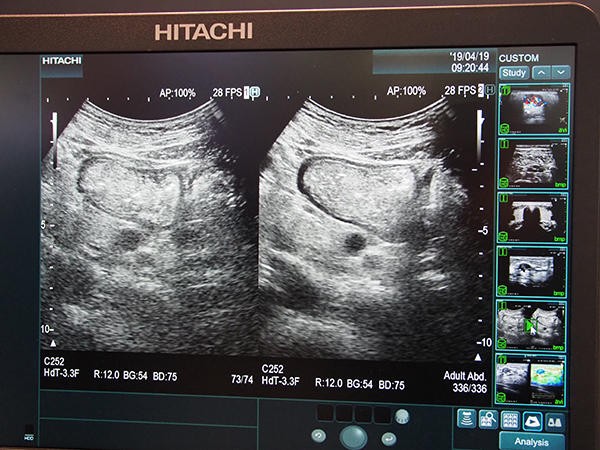

そして今回,新しく“Carving Imaging”が紹介された。ハイエンド装置として,より高精細な画像へと進化を深めるだけでなく,被検者依存/検者依存しやすい超音波装置だからこそ,“見えにくいものを見やすくする”ために開発されたアプリケーションである。体格の大きい被検者や,ノイズが乗りやすい脈管などの領域において,ノイズを低減し,高コントラストで辺縁をはっきりとさせる画像処理が可能になり,視認性の高い画像を表示することができる。日米ともに2019年から提供が開始されており,ARIETTA 850に加え,上位機種の画質性能などを引き継いだコンパクト装置ARIETTA 65でも,最新バージョンから対応可能となった。

視認性を高める“Carving Imaging”

Carving Imagingで表示した甲状腺